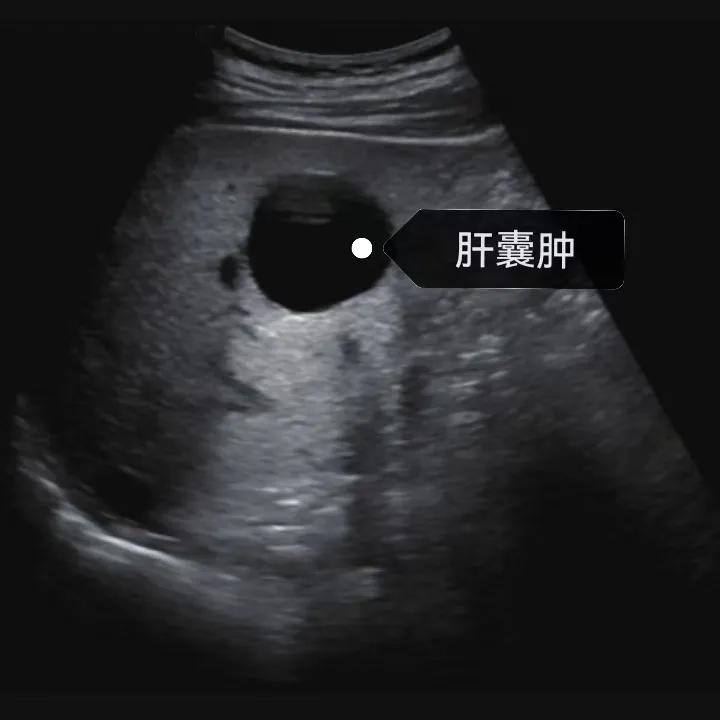

肝囊腫是一種常見的肝臟良性疾病,呈圓形或橢圓形,外由上皮細胞包裹形成包膜,內(nèi)由清亮、無色、無細胞成分的囊液填充,看上去就像是一顆注滿了水的氣球,因此通俗一點說就是肝臟中的“水泡”。

超聲通常是診斷肝囊腫的首選方法,彩超對肝囊腫的檢出率可達98%,<1cm的囊腫也可檢出。肝囊腫常表現(xiàn)為圓形或橢圓形無回聲,包膜光滑完整,邊界清晰,可有側(cè)壁回聲失落征象,后方回聲增強。病程長、囊腫較大者或囊內(nèi)有過出血、感染者,無回聲腔內(nèi)可見少量絮狀回聲漂浮。超聲對肝囊腫的診斷準確而靈敏,且方法簡單、無創(chuàng)、費用低、可重復(fù)性高,因此常常被作為首選。